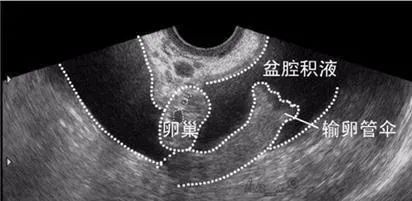

盆腔积液 是一种表现,而不是一种疾病 ,是指女性盆腔内有液体存在。盆腔积液可分为生理性盆腔积液和病理性盆腔积液。

盆腔是腹腔在 全身较低的部位 ,当腹腔脏器有渗出液、漏出液或破裂出血时,首先会引流到盆腔,形成盆腔积液。例如,一些健康的女性在 排卵期 或 月经期 可能会有少量的液体积聚在盆腔,形成盆腔积液,这样的积液一般都是生理性的, 多数可自行消失 。

如果B超检查显示有盆腔积液,同时患者伴有如 下腹疼痛、腰酸下坠、下腹胀痛、坠痛、腰酸、白带多 ,妇科检查子宫、附件有压痛,宫颈有充血等,则可能是 炎症引起 的,这样的积液是病理性的。